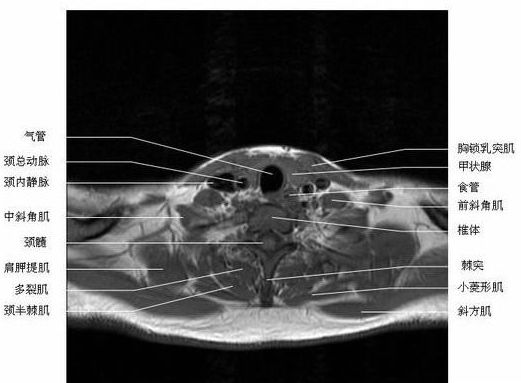

头颈部横断面-MRI图片

头颈部横断面-MRI图